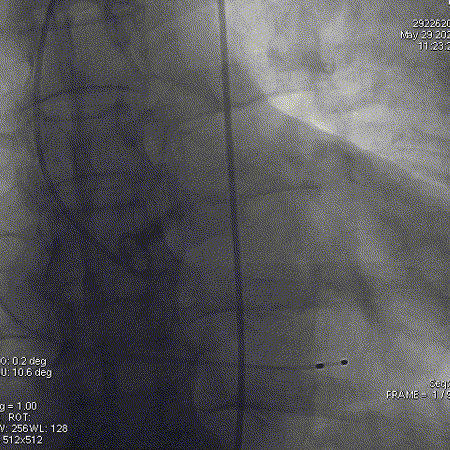

导丝跨瓣

球囊预扩